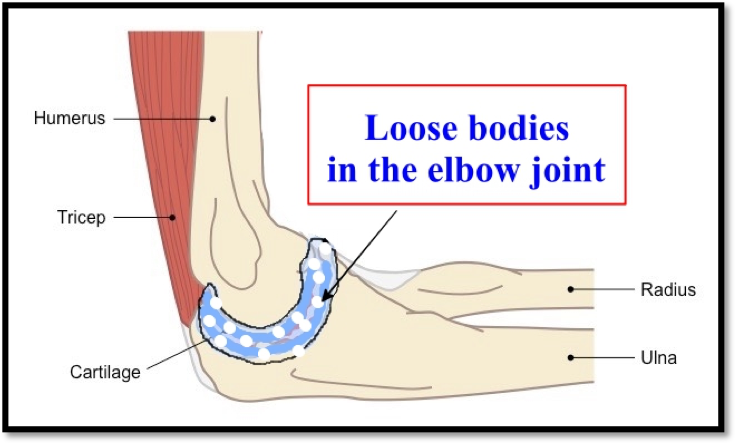

The elbow joint is formed by 3 bones- one arm-bone (Humerus) and two forearm bones (Radius, ulna). Like other joints the two bones are connected by ligaments and surrounded by muscles.

In this condition the blood supply to a small part of the bone with the cartilage on top of it gets interrupted. This part of bone and cartilage becomes dead. In some patients the blood supply gets restored and the lesion heals. This is usually in adolescents and young patients. In older patients the dead bone and cartilage get separated and form loose body in the joint.

This condition is seen in young patients between the ages of 20-45 years. The inner lining of the elbow joint starts to abnormally produce excess cartilage and bone like tissue. Normally this lining produces a lubricating fluid. These cartilage-like loose bodies within the elbow joint initially irritate and then abrade the cartilage of the joint. Cartilage is the protective covering over the joint surface. Loss of this protective covering leads to arthritis and damage of the elbow joint.

7. What are loose bodies?

These are free pieces of bone or cartilage, which lie within the elbow joint. They are like pebbles in a flowing river. They move within the joint with joint movement. A foreign body in the eye irritates the eye and the eye turns red and painful. Similarly a loose body in a joint irritates and over a long period of time causes destruction and arthritis of the joint.

8. How does a loose body come in the elbow joint?

Usually a loose body enters the elbow joint after a significant elbow joint injury like road accident or fall from height, which causes a fracture of either bone of the elbow joint. The other cause is synovial osteochondromatosis.